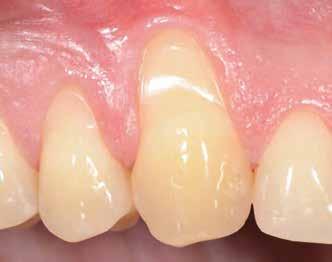

Preoperatív helyzet

Egy fiatal páciens jelentkezett nálunk, akinek eltörött a szabad véggel rendelkező hídja (1. ábra). A hiányzó, első premoláris fog esetén implantációs pótlást javasoltunk. A csontállomány értékeléséhez CBCT-vizsgálatot végeztünk, és az elemzéséhez NNT Viewert (NewTom) használtunk, és copaSKY 4×10 mm-es (bredent medical) implantátumot választottuk a fog pótlásához

1. ábra: Műtét előtti fogászati panorámafelvétel, amelyen a hiányzó felső állcsont jobb első premolárisát és a szabad véggel rendelkező hidat láthatjuk. — 2. ábra: Az implantátum méreteinek megtervezése CBCT-vel. 3. ábra: Bukkális lágyrészdefektus. — 4. ábra: A biológiai szélesség értékelése a vertikális lágyszövetvastagság alapján. 5. ábra: Palatinális „tekercslebeny” – Palatal roll flap. — 6. ábra: Bredent medical copaSKY 4x10 implantátumbeültetés. 7. ábra: Szubkresztális implantátumbeültetés a várható biológiai szélességnek megfelelően.

(2. ábra). A lágyszövetek értékelése Seibert szerinti I. osztályú csontdefektust állapított meg (3. ábra), ezért a beavatkozáskor palatinális „tekercslebenyt” preparáltunk (palatal roll flap), és implantációt végeztünk, hogy kompenzálni tudjuk a bukkális lágyszövet-behúzódást. Megmértük a vertikális lágyszövetvastagságot, és úgy terveztük, hogy a szubkresztális implantátum beültetése összhangban legyen a biológiai szélesség kialakulásával a transzgingivális gyógyulási periódus alatt (4. ábra)